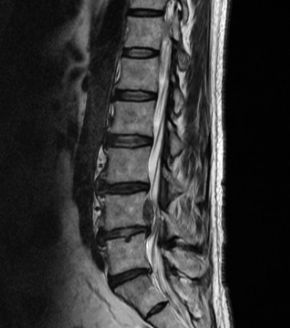

허리디스크를 정확하게 진단하기 위해서는 엑스레이로는 힘들며, MRI를 통해 검사해야 정확하게 볼 수 있습니다.

MRI가 몸에 좋지 않지만 허리 통증으로 엑스레이만 진행할 경우 오진이 많아 지속적인 통증이 계속된다면 허리디스크를 의심하고 MRI 검사를 한번 받아보시길 권유드립니다.